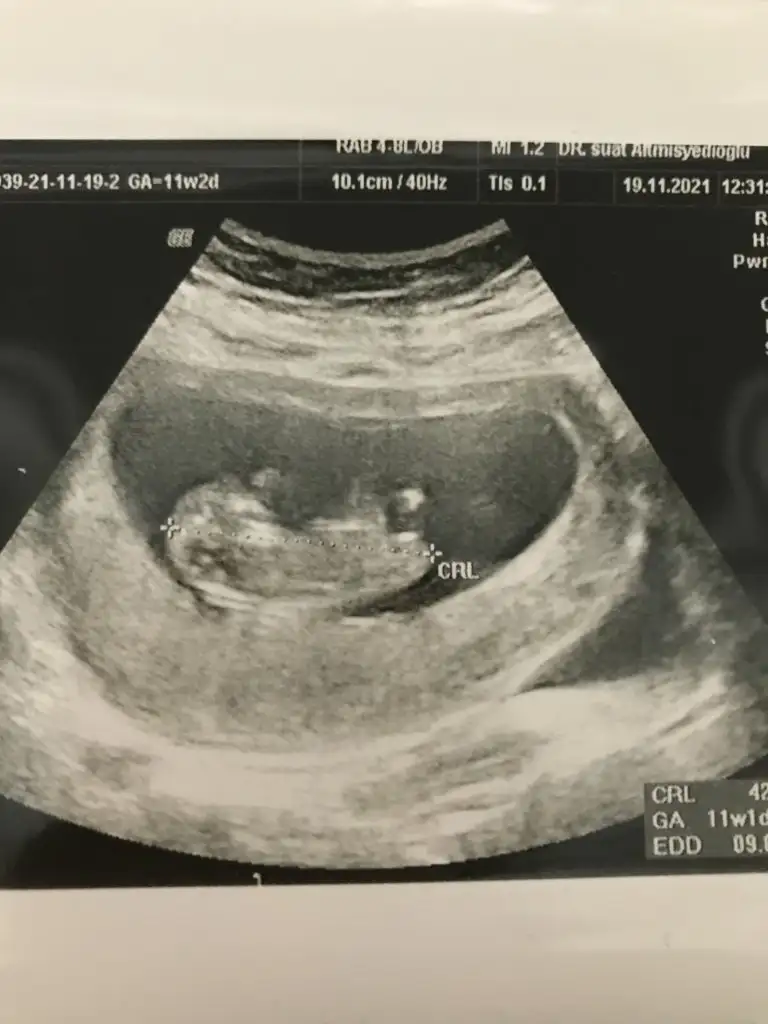

Kuzum tahmin edebilecek misin 12+5 en net resmi 🤷

Eklentiler

• IMG20210922120304.webp

IMG20210922120304.webp

26,2 KB · Görüntüleme: 116

Kızlar bı arkadaş keseye göre tahmin yapıyor ve hep tutuyormuş iki oğlunu da bu şekilde cok yeniyken bile tahmin etmiş...ogullarinda kesesi hep uzunmuş muz gibi...yuvarlak ve yuvarlağa yakın olanlar hep kızdır diyor..ve bayağı emin konusuyor..benimki şişman bı fasulye gibi oo kesin kız görürsün dedi...sizlerin keselerinin şekli nasıldı ve cinsiyet neydi konusalimmi 😊